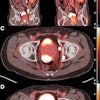

The product contains a novel type of digital bismuth germanate (dBGO) detector material with a small crystal size that delivers more than two times the sensitivity of prior digital scanners, enabling faster total scan times and improved small lesion detectability, according to the vendor.

GE states that Omni Legend 32 cm increases small lesion detectability by 16% on average and up to 20%, as compared with the Discovery MI 25 cm with matched scan time/injected dose, as demonstrated in phantom testing using a model observer with 4 mm lesions.

Also included in the scanner is the Q.Clear PET image reconstruction software and MotionFree, GE's respiratory motion correction technology. Q.Clear reportedly helps to ensure reliable quantification, while MotionFree can correct respiratory motion artifacts for all patient types, the company adds.